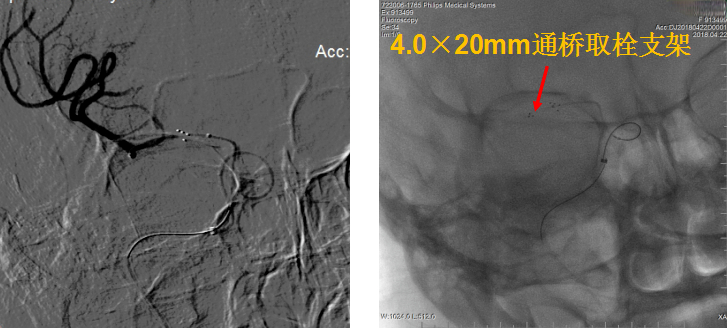

考虑血栓负荷量大,遂采用双支架取栓技术。

该病例为颈内动脉C1段远端闭塞,血栓负荷率大,我们采用常规的SWIM技术(支架取栓+抽栓),但是效果不佳,于是改为双支架串联技术取栓,达到mTICI 2b级血管再通效果。

针对本例患者,选择了单纯使用导引导管的双支架串联式释放同时局部并联释放技术,双重支架叠加可以增加支架释放的径向支撑力,同时也增加了支架网丝对血栓的嵌入效应、接触面积和血栓的缠绕能力,快速将血栓拉出体外,提高了开通效率,并最终获得良好开通效果和3个月良好预后。